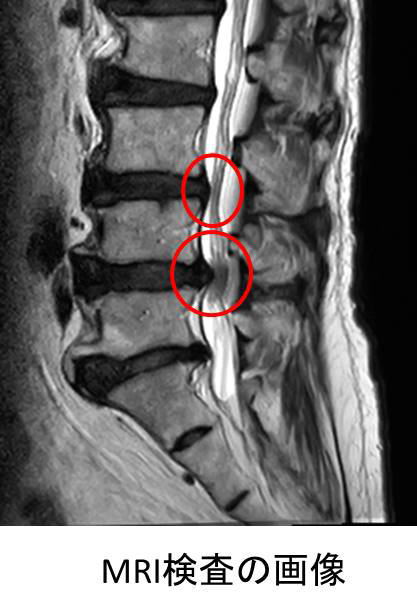

脊柱管狭窄症

腰椎椎間板ヘルニア